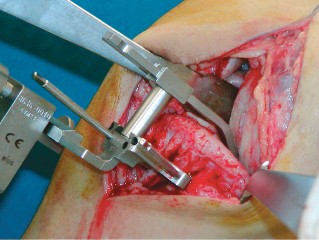

2. الوضع الجراحي والتعرض

- الوضع: يُوضع المريض في وضع الاستلقاء (Supine positioning) مع وضع كيس رمل أسفل الركبة أو حامل للساق يسمح بثني وفرد الركبة. يجب أن يكون الوضع مماثلاً لوضع جراحة TKA، مع استعداد لتحويل الإجراء إلى TKA إذا لزم الأمر.

- العاصبة (Tourniquet): تُستخدم عاصبة وتُوضع في أعلى الفخذ لتقليل النزيف.

-

الشق الجراحي:

يُستخدم شق طولي في الجانب الإنسي (الداخلي) من الركبة. يجب أن يكون الشق كبيرًا بما يكفي لتوفير رؤية جيدة للمفصل الرضفي الفخذي وإمكانية التحويل إلى TKA.

- فتح المفصل (Arthrotomy): يكون الفتح خطيًا وموازياً لألياف الوتر الرضفي، ويمتد إلى عظم الظنبوب وإلى الجزء السفلي من الرضفة.

- تحرير الأنسجة الرخوة: يتم قطع الغضروف الهلالي لتحرير الأنسجة الرخوة من عظم الظنبوب، ويتم تطوير سديلة تحت السمحاق في نمط دائري حول الظنبوب. يُمدد هذا التحرير خلفيًا لضمان توازن الأربطة.

-

تصحيح التشوه:

الهدف هو تحقيق تصحيح طفيف للتشوه، مع وجود رخاوة كاذبة طفيفة عند تطبيق ضغط تفحجي في نهاية الإجراء. يجب تجنب التصحيح المفرط.